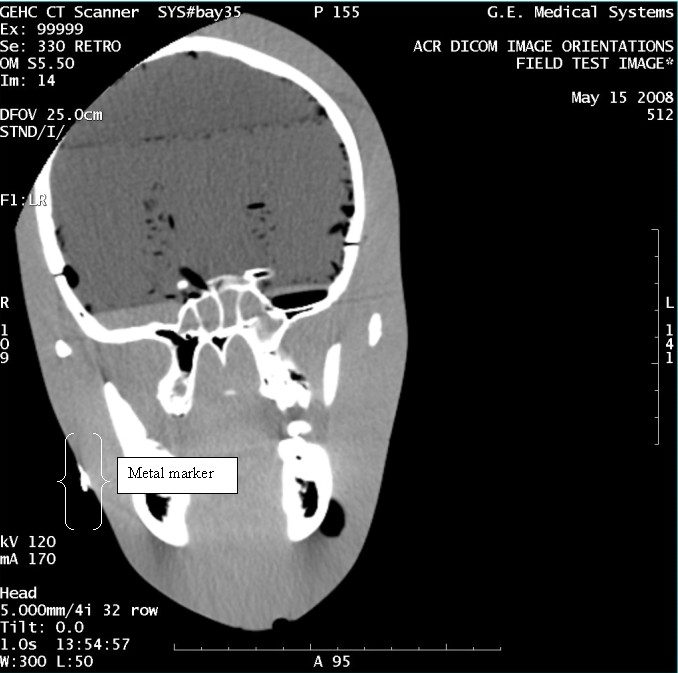

- With the support of the site personnel, examine the images sent

to the Review Station (i.e., 12 series, each with 1 image) and compare

their orientation to the images in this document.

- Each image contains a metal marker on the phantom's right cheek.

- Each image in this document contains a description of the expected

orientation of the metal marker (i.e. to prove Left and Right) as

well as the Posterior and Anterior orientation description.note:

The sample images included in this document use “R”, “L”, “P”, and “A” for “Right”, “Left”, “Posterior” and “Anterior” orientation. The Hospital Review Station may use a different style of annotation. The style used is not relevant to this procedure.

- Each image in this document has sufficient space to store the observed results for up to 4 Review Stations.

- Enter ‘Y’ in the space to indicate the observed result matches the expected.

- Enter ‘N’ in the space to indicate the observed result does not match the expected.

- Enter “NA” in the space if a column is not being used.

- Repeat for each destination.

Figure 8. Exam 99999, Series 330

Figure 9. Exam 99999, Series 339